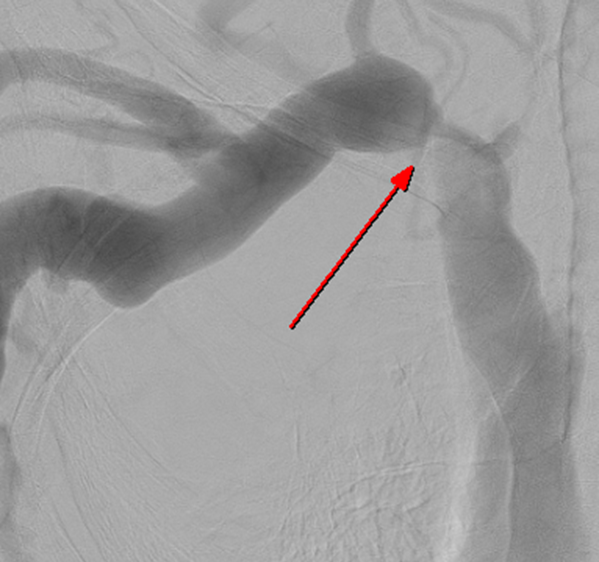

투석혈관 기능부전은 여러가지 이유로 투석혈관이 좁아지거나 막히는 현상을 말합니다.

동맥과 정맥의 압력 차이 때문에도 혈관이 좁아지고, 수술 중 (굉장히 조심하시지만) 혈관에 자극이 가서 연결 부위가 좁아지는 경우도 있고, 연결 했음에도 투석 혈관이 미성숙해서 넓혀지지 않는 경우도 있습니다.

경피적 혈관성형술이란 피부를 미세 절개한 뒤, 직접 혈관으로 접근해서 좁아진 혈관을 확장해주는 시술입니다.